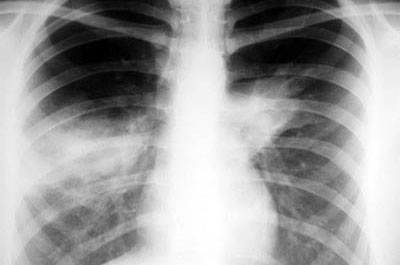

Рентген здоровых легких фото с описанием выглядит однородным и равномерным, в противном случае нездоровые органы, завися от характера изменения, на снимке могут быть затемненными или . . .

Как выглядит воспаление легких на рентгеновском снимке и ее признаки проявления .

Как выглядит пневмония на рентгеновском снимке . Достоверность диагностики рентгена при пневмонии у взрослых и детей . Примеры описания рентген снимков при пневмонии, какие рентген-признаки указывают на патологию .

На снимке вместо белого появляется темное пятно . Если снимок рентгена легких показывает, что видны черные пятна, это говорит об обострении и наличии хронического воспаления легких . После . . .